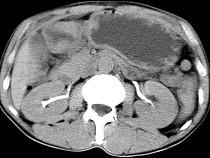

问题 男,56岁,无规律上腹痛,左锁骨上淋巴结肿大,消瘦、乏力,影像检查如图,最可能的诊断是 ( )

选项 A.腹膜结核 B.胃溃疡穿孔 C.胃癌并盆腔种植 D.胃及腹腔淋巴瘤 E.肠系膜淋巴管瘤

答案 C